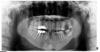

Olga_ Опубликовано 7 августа, 2012 Поделиться Опубликовано 7 августа, 2012 Здравствуйте! У мужа такая проблема- после установки моста (сверху) часто болела десна. Честно говоря, сначала грешили на то, что могли не удалить полностью зуб, и боли связаны с ним, так как зуб был не целиковый был и то, что он удален не полностью смог заметить только ортопед перед установкой моста. Подумали, что тогда часть корня могли вытащить, а часть всё же осталась, тем более, что мост ставили сразу после удаления кончика зуба.Десна над мостом болела 1,5года, врачи, которые устанавливали, говорили, что всё в порядке. Посоветовали лучше ухаживать за коронками -пользоваться ирригатором. После первого же применения ирригатора вздуло щеку. Муж пошел уже в другую клинику на консультацию -хирург сделал орто, патологии не заметил.После этого через некоторое время на десне появилась шишечка,похожа на свищ (над более дальним, где 3 канала).Прошу посмотреть -из-за чего он мог образоваться (хорошо ли пройдены каналы) и если где-то всё же не пройден есть ли шанс (сколько процентов) его перелечить.Заранее спасибо.Снимок прилагается, от 30.06.2012. 1 Ссылка на комментарий

Magdalena Опубликовано 8 августа, 2012 Поделиться Опубликовано 8 августа, 2012 Сделайте прицельный снимок 16 зуба, по данному снимку впечатление, что есть воспалительный очаг на верхушке одного из корней, причиной может быть не найденный или непройденный 4 канал. Ссылка на комментарий

Magdalena Опубликовано 14 августа, 2012 Поделиться Опубликовано 14 августа, 2012 Ольга, на снимке тоже видно 3 канала, просто один немного на другой "наслаивается". На верхушке одного из корней есть воспалительный очаг, от этого может быть свищ. Скорее всего, не прошли (или не нашли) 4 канал, по снимку его не всегда можно увидеть, обнаруживают в процессе лечения. Не пройденный канал можно увидеть на 3Д-компьютерной томограмме. Перелечить зуб можно, можно сделать двумя способами1. сделать доступ к каналам через коронку, перелечить и потом это отверстие в коронке закрыть пломбировочным материалом.2. снять мостовидный протез, пролечить зуб, изготовить новый протез, или 2 одиночные конки на 16 и 14 зуб и в области отсутствующего зуба поставить имплантат (так или иначе зубы в "мостике" находятся в состоянии перегрузки). 2 вариант более предпочтителен.К сожалению, дать гарантии, на то, что воспалительный очаг после лечения пройдет, и зуб простоит всю жизнь, никто не может. Единственный гарантированный вариант - удаление с последующей имплантацией. Ссылка на комментарий

Magdalena Опубликовано 30 августа, 2012 Поделиться Опубликовано 30 августа, 2012 (изменено) Ольга, в зубе пропущен 4 канал. Даже если посмотреть на не леченный симметричный 26 зуб в поперечном разрезе - он 4-х - корневой и 4-х-канальный, а строение симметричных зубов, как правило, одинаковое. Утолщение слизистой правой гайморовой пазухи возможно и как реакция на выведенный материал, но скорей всего на наличие воспалительного очага, а возможно было и ранее, при наличие хронического воспаления (гайморит и т.д.).Зуб нужно перелечивать, желательно , чтоб врач владел возможностью лечить с микроскопом. По снимку ход канала виден, канал проходим, возможно для доступа придется распломбировать медиальный щечный канал (запломбированный канал в том же корне). Лечение должно быть в несколько этапов - чистка и промывание канала, закладывание лечебной пасты на основе гидроокиси кальция на 2-3 недели и затем постоянное пломбирование. Изменено 30 августа, 2012 пользователем Magdalena Ссылка на комментарий